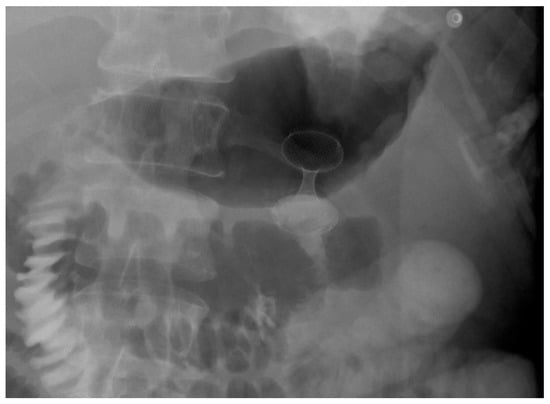

4. Gastroduodenal Tract—Gastric Outlet Obstruction

4.1. Malignant GOO

- Type I: Stenosis at the duodenal bulb without papillary involvement.

- Type II: Obstruction in the second part of the duodenum involving the papilla—requiring combined palliation of both gastric obstruction and biliary drainage.

- Type III: Obstruction in the third portion of the duodenum, sparing the papilla [115].

4.1.1. Role of Stent

Indications and Mechanism of Action

Efficacy and Adverse Events